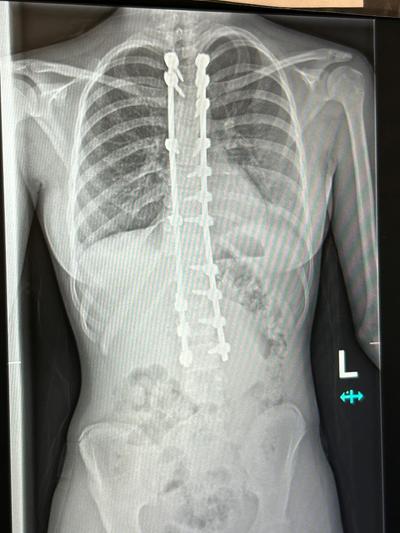

The surgery fitted Bode with one titanium and one cobalt chrome rod on either side of her spine held in place by 18 screws. “Comparing the before and after X-Rays, they managed to make my spine perfectly straight which was incredible."

X-ray.jpg  X-ray 2.jpg